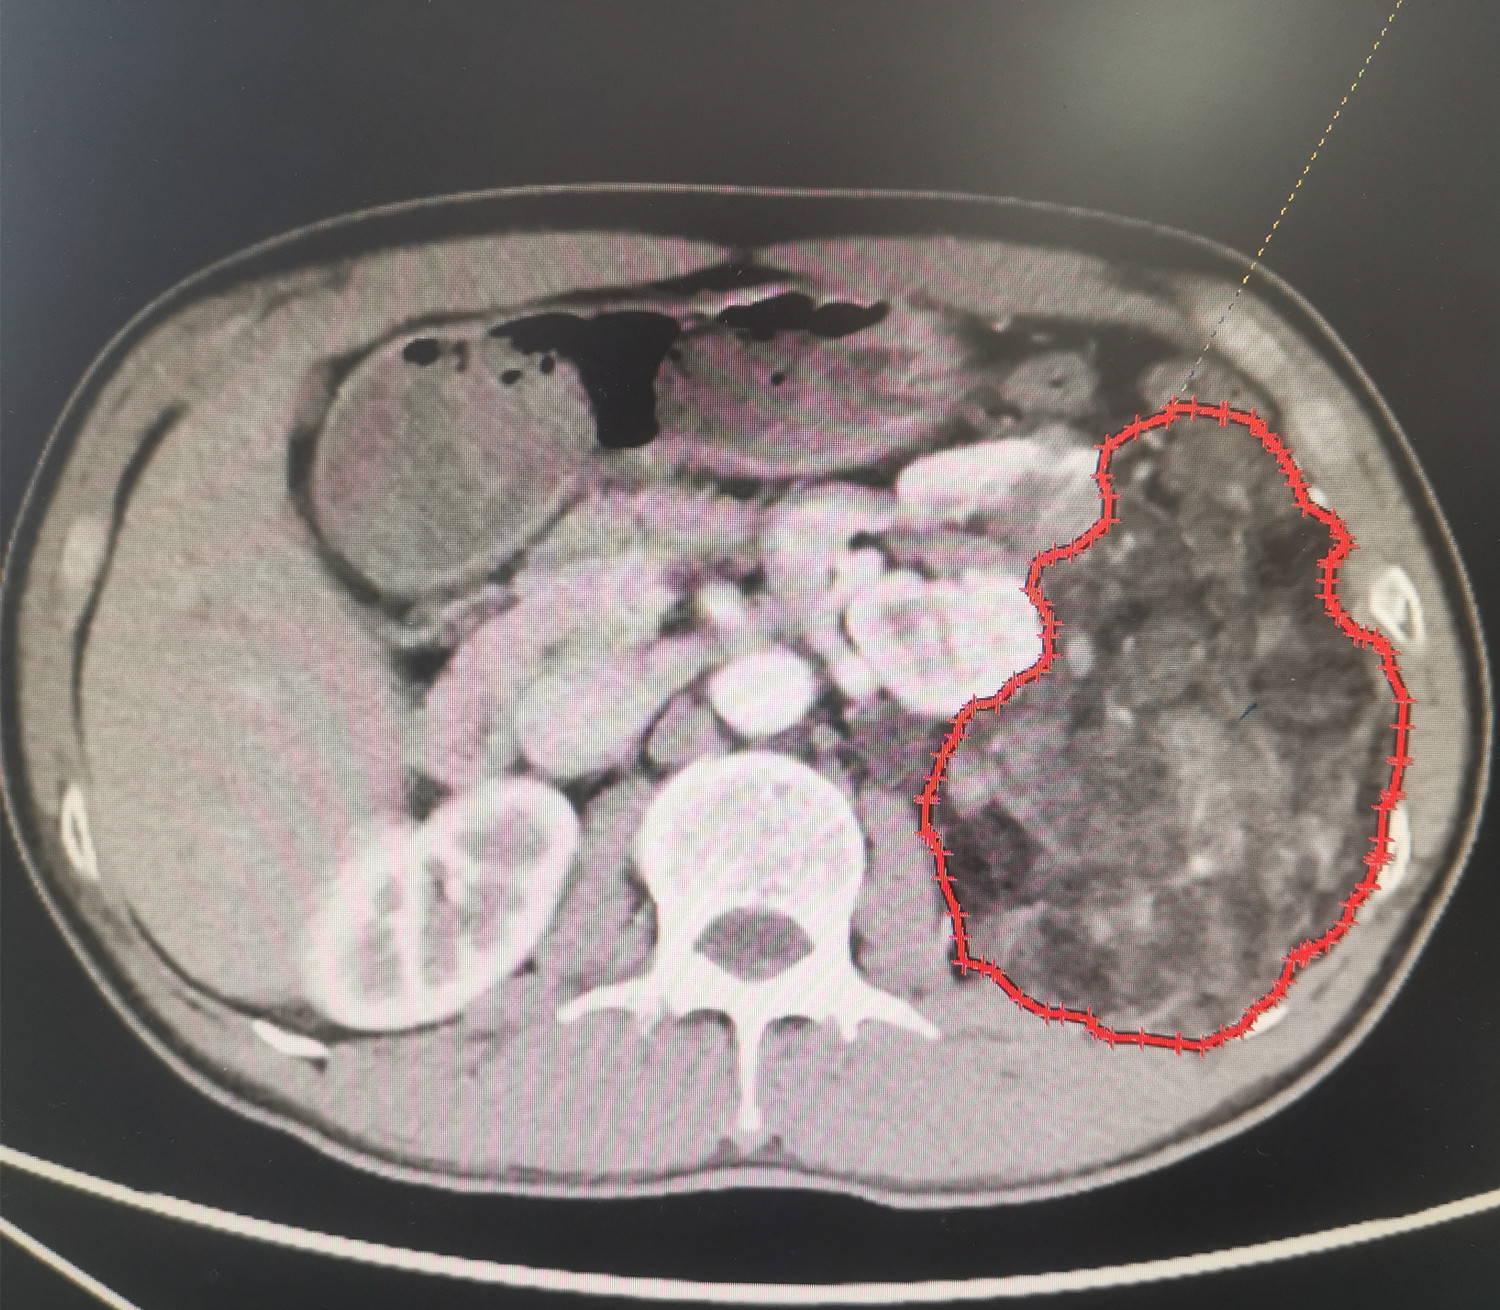

圈出部分为左肾上的巨瘤

李先生在单位例行体检时,意外发现左肾竟有一个20×16厘米的占位。经过泌尿系彩超、泌尿系CT等检查,基本确诊患上的是肾错构瘤。“平时也没啥症状,怎么肾脏上就长这么大的瘤子。”李先生表示很意外。